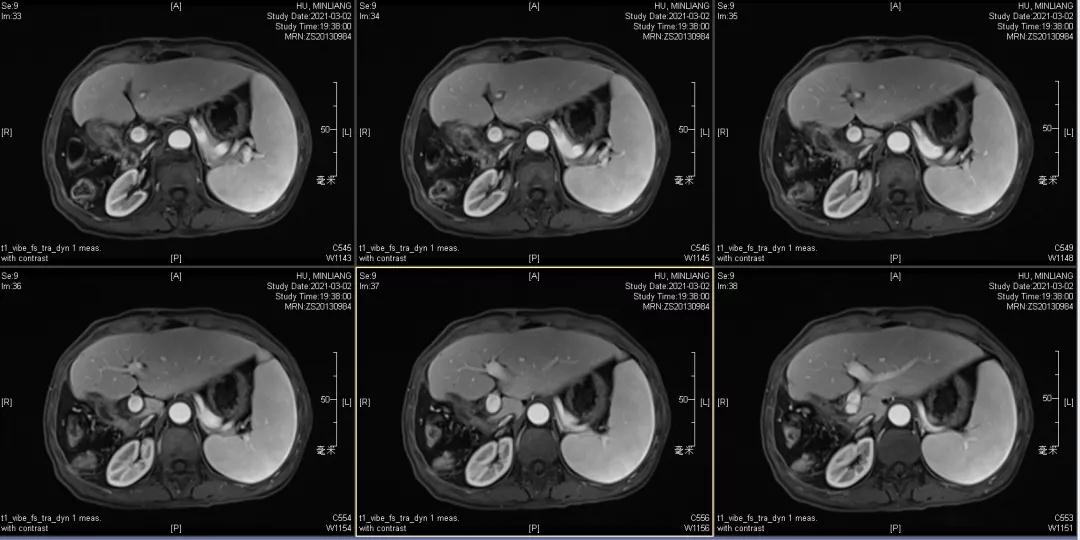

用药6个月后:肝脏病灶明显缩小,子灶消失,仅有少量动脉期强化;肺转移单个持续缩小稳定,PET CT活性弱;HBV DNA 转阴;可考虑转化切除。

2021-2-1 手术切除:右半肝切除术+胆囊切除

术后病理:病理学CR

术后1月复查:磁共振肝内未见肿瘤复发,肺部单个肿瘤稳定。

术后末次随访2021年12月6日,肝内未见明显病灶,肺部病灶稳定1.3cm。

目前OS 17个月,RFS 10个月。

Δ末次随访MRI及AFP变化